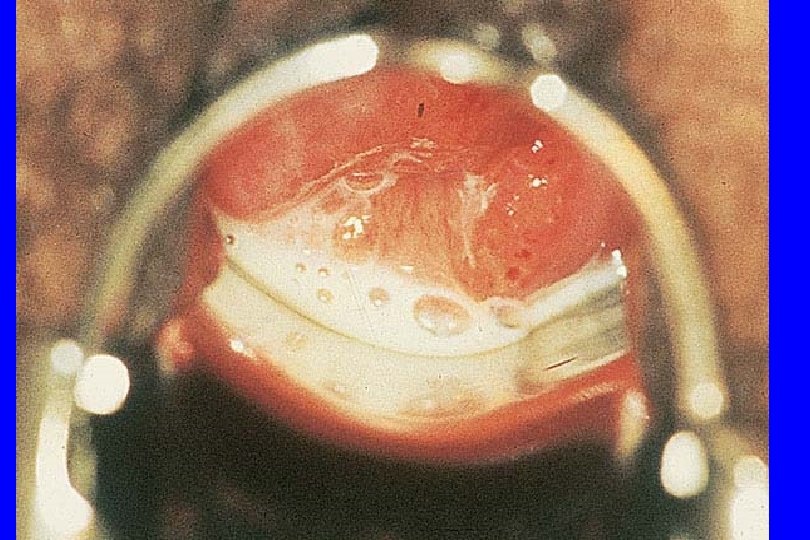

The Cervix and Trichomoniasis l Classic: “strawberry cervix” Ø Focal areas of superficial hemorrhage surrounded by paler mucosa Ø May also see more subtle petechiae Ø More common with relatively moderate-severe Trichomonas vaginitis

Cervicitis due to Trichomonas vaginalis